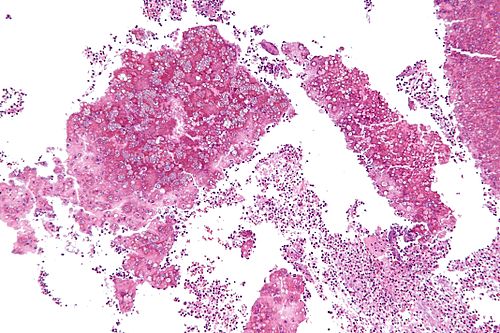

Intermediate magnification

Intermediate magnification. H&E stain.